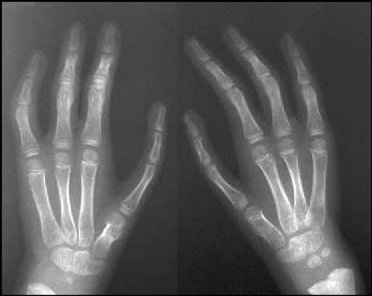

| Case 3. (case of unknown surgeon). The index fingers were probably narrow to begin with, and the current metacarpal length detract from the final result. |

![]() |